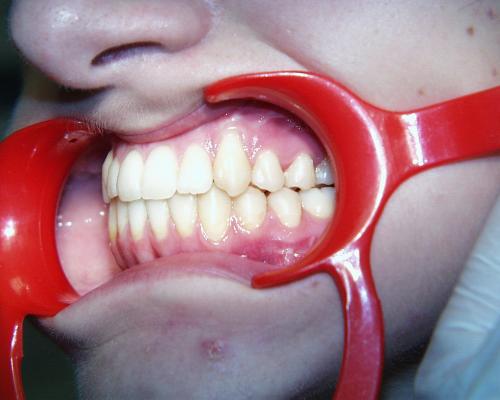

Während der Behandlung

Linkes Bild kurz vor, rechtes Bild kurz nach der Operation. Häufig ist noch eine weitere Anpassung der Zahnbögen und eine Feineinstellung der Verzahnung notwendig. In der Regel müssen die Patienten zwischen den Zahnreihen kleine Gummiringe einhängen, um die Kiefer in der gewünschten Position zu halten.